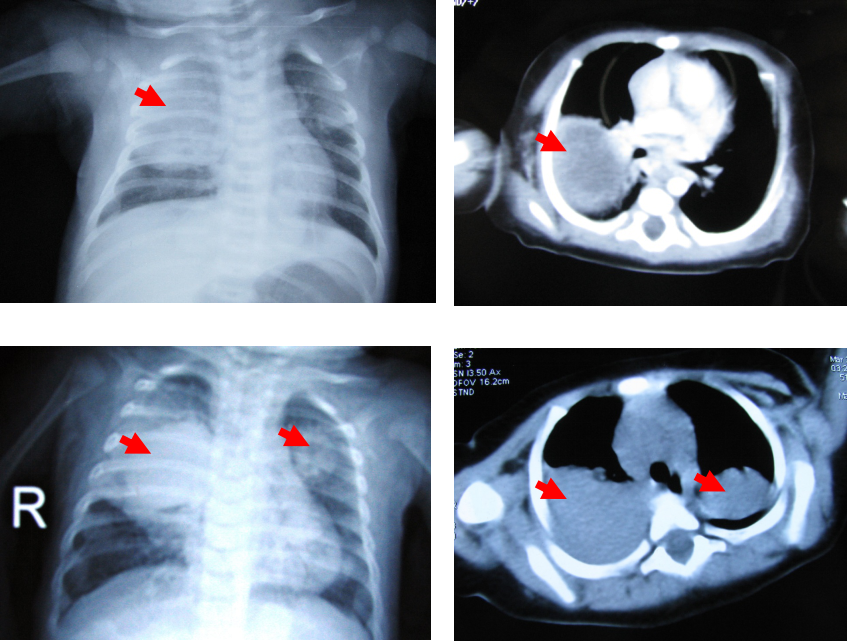

CGD患儿BCG感染和PPD试验

CGD